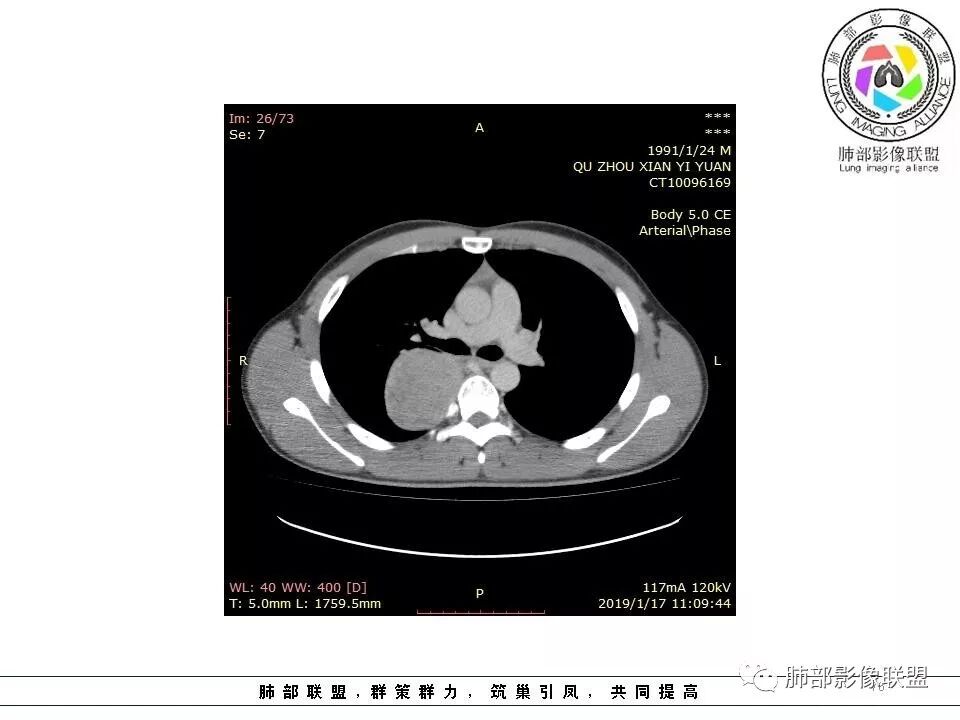

右后纵膈脊柱旁软组织占位,形态规则类圆,边缘光整,肺组织受压,胸膜尾,肋间动脉供血。中度不均匀延迟强化。

右后纵膈脊柱旁软组织占位,边界清晰,光整,肺组织受压。胸膜被掀起,肋间动脉供血,中度不均匀延迟强化。考虑神经鞘瘤,不除外纤维瘤

右后纵膈脊柱旁软组织影,与纵隔结构分界不清,形态规则类圆,边缘光整,肺组织受压,胸膜尾,肋间动脉供血。肺动脉推移,中度不均匀延迟强化。考虑神经来源,神经鞘瘤,神经纤维瘤二者不易鉴别。

青年男性,间断胸痛;右侧脊柱旁可见一类圆形软组织密度影,密度欠均匀,增强扫描呈轻中度持续强化,邻近肺组织及肺动脉推移,可见肋间动脉供血,部分胸膜下脂肪可见,部分层面似见与右侧椎间孔相连。考虑后纵隔神经源性肿瘤。

青年男性,间断胸痛。右后纵膈脊柱旁软组织占位,形态规则类圆,边缘光整,肺组织受压,D字征,胸膜尾,肋间动脉供血。中度不均匀延迟强化。无支气管进入考虑来源于肺外、肿块与脊柱间未见明显脂肪间隙,考虑来源于胸膜外,考虑神经源性肿瘤,建议穿刺活检。

青年男性,右侧脊柱旁软组织肿块,边缘膨隆,密度不均,临近肺组织受压、胸膜增厚,增强后动脉期呈不均匀强化,并可见肋间动脉供血,延迟期强化较均匀,定位肺外,首先考虑SFT,神经源性肿瘤待排

年轻患者,偶胸痛,巨大肿块,无明显纵膈淋巴结肿大,无明显胸腔积液,考虑良性或低度恶性肿瘤。30.8-44-58-61hu,渐进性强化,边缘光滑,平扫密度不均,增强密度不均,纤维可以渐进性强化,不强化(或低密度去)区,为粘液。考虑孤立性纤维腺瘤伴粘液。

或者是某种肿瘤的坏死,但坏死不明显,低密度区呈湖泊样,巨淋巴结增生,与性质有关。

血管贴边征,邻近血管未明显增粗,体循环可能,其内血管未破坏,血供丰富,不除外血管源性。

右侧脊柱旁软组织肿块,胸膜尾征,肺动脉受压推挤,肺组织边缘清晰,增强,肿块由肋间动脉供血,延迟期强化不均匀,内见斑片状低密度区,定位肺外,后纵膈,神经源性肿瘤可能性大,鞘瘤?

青年男性,右侧脊柱旁占位,瘤肺界限清晰,支气管推移,胸膜尾,D字征,胸膜下脂肪影,蛇纹血管,双重供血,延迟强化,定位胸膜,支持sft

肋间动脉供血,强化尚均匀,逐步强化

1.右上胸内脊柱旁类圆形肿块,质地似乎比较坚实,密度稍显不均,但未显示明确的坏死。

如此密度形态的病灶位于肺边缘首先应当想到孤立性纤维瘤,可相邻胸膜未见明显的异常强化和胸膜方向延伸。

2.肋间动脉病供血也提示肿块来自后纵隔?

4.静脉期轻度不均匀强化,注意不是环形强化,亦未见明确的“AB区”,这点也不支持神经鞘瘤。临床及病灶轻度强化都不支持副节瘤。

尽管神经纤维瘤的诊断确实有些出乎意外,但病例开阔了我们的视野。